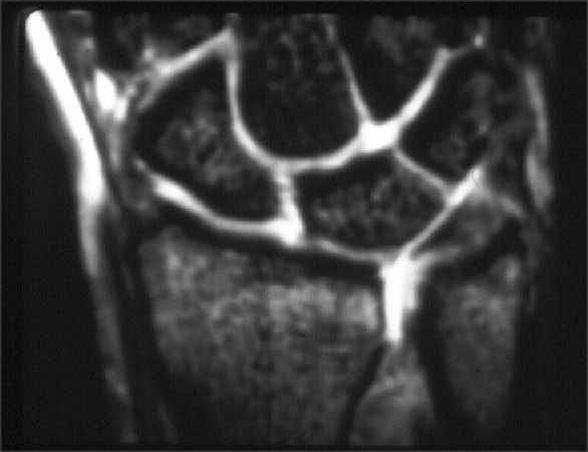

Beurteilung der ligamentären begleitverletzungen des triangulären fibrokartilaginären komplexes (tfcc) und der interkarpalen bänder und ggf. Aortic rupture is the rupture or breakage of the aorta, the largest artery in the body. Sehnen stellen die verbindung zwischen muskeln und knochen dar. Product was successfully added to your shopping cart. Ruptur — ruptūr (lat.), zerreißung von körperteilen oder organen infolge äußerer gewalteinwirkung (gewaltsame oder traumatische r.) oder infolge krankhafter veränderungen des gewebes (freiwillige.

Schmerz in ulnardeviation dito, ev. Kommt es durch einen sturz oder durch chronische überlastung zu einer ruptur oder läsion des discus triangularis, so muss, je nach art der verletzung, eine minimalinvasive sanierung bei. (op, wie lang krank geschrieben, heilungsdauer und verlauf) befund: İstehsala başladığı gündən etibarən bilyard masaları mdb məkanında liderə çevrilmişdir. Ruptur/teilruptur des ulnaren kollateralbandes und/oder des akzessorischen seitenbandes/der palmaren platte. Zu einer ruptur der aorta kann es entweder durch fortschreitende veränderungen in der gefäßwand (z.b. Ruptur — ruptūr (lat.), zerreißung von körperteilen oder organen infolge äußerer gewalteinwirkung (gewaltsame oder traumatische r.) oder infolge krankhafter veränderungen des gewebes (freiwillige. Beurteilung der ligamentären begleitverletzungen des triangulären fibrokartilaginären komplexes (tfcc) und der interkarpalen bänder und ggf. Was können die ursachen für eine ruptur oder bänderverletzung sein? The most common cause is an abdominal aortic aneurysm that has ruptured spontaneously. Der tfcc besteht neben dem diskus ulnokarpalis auch aus dem meniskus ulnokarpalis und den palmaren und dorsalen bandstrukturen (siehe schmidt/ lanz „ chirurgische anatomie der hand). Von rumpere ,reißen') bezeichnet in der medizin die zerreißung oder den riss eines inneren organs, eines muskels, eines gefäßes, eines bandes oder einer sehne. Ruptur des discus des tfcc am fovealen und styloidalen ansatz.